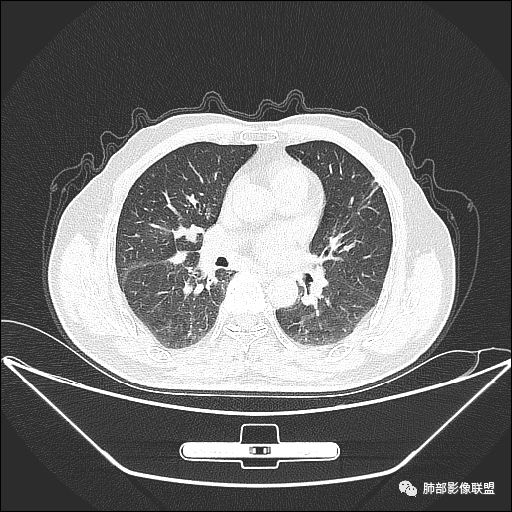

住院4天后行胸部增强CT

老年男性,因“咳嗽咳痰1月余。”入院。病程中咳嗽咳痰,咳黄白痰,间断咯少许鲜红色痰血。PPD阳性。胸CT:右肺中叶外侧段支气管管腔阻塞,大片实性病变,病灶边缘光滑,部分边缘膨隆,可见分叶,肺门及纵隔可见肿大淋巴结,并可见钙化。增强可见病灶明显强化,而且延迟强化明显,病灶内多发低密度区,内见血管影,血管变细、部分血管破坏。考虑恶性病变可能性大,鉴别慢性肉芽肿性病变。

右肺中叶外侧段管腔阻塞、实性病变,病灶边缘光滑,可见分叶,肺门及纵隔可见肿大淋巴结,并可见钙化。增强可见病灶内多发低密度区。

老年男性,咳嗽、咳痰1月余,间断血痰。PPD阳性。

胸CT:跨叶大肿块,主体在中叶,右中叶外侧段支气管阻塞,病灶部分边缘膨隆,可见分叶,部分边缘平直,肺门及纵隔可见肿大淋巴结。增强病灶不均匀强化,延迟强化明显,病灶内多发低密度区,内见血管飘浮,部分血管变细、模糊。考虑:恶性病变可能性大,大细胞?淋巴瘤?鉴别慢性肉芽肿性病变。

右肺中叶软组织肿块,外围向内生长,叶间胸膜向前内移位,肿块近肺门侧跨叶,中叶外侧段支气管截断,密度不均匀,双侧肺门及隆突下见肿大淋巴结,增强后呈中度不均质强化,肺动脉供血,多发坏死区,边界尚清,坏死区域内见结构,结合病史考虑恶性,鉴别诊断1结核,爬行征是沿支气管树分布,外宽,内窄,周围有卫星灶,内气管狭窄后扩张,此例沿叶间胸膜长轴分布,气管有截断,不典型。2炎性肉芽肿,符合的地方下方层面增强后延迟性轻度环形强化,不符临床无发热等急性感染病史,实验室指标不符,病灶周围渗出及慢性炎性改变有,不明显。

我们现在看主病灶,病灶紧贴叶裂:

我想看冠状位,就是看它长轴、病灶的整体形态

外围大、内带小

这时候我认为支气管最重要

支气管进入其中,远端粘液栓

我认为鉴别:结核?腺癌?